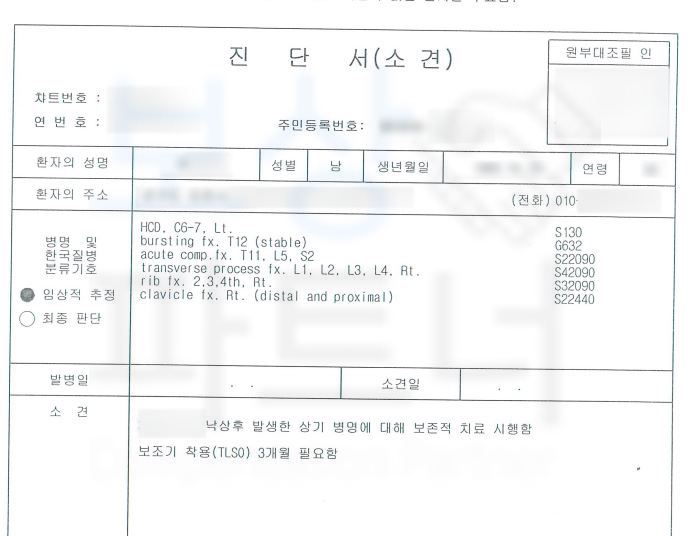

영문으로 된 진단서를 풀어드리자면 C6-7 HCD -> 경추 디스크 S130 Bursting fx. T12 -> 흉추12번 척추골절 Acute comp.fx T11, L5, S2

-> 흉추11번 요추5번 천추2번의 급성 골절

Transverse process fx -> 횡돌기 골절 Rib fx. / clavicle fx -> 갈비뼈 골절, 빗장뼈 골절 다발성 골절로 인해 최소 12주간 입원 및 요양을 하셔야 했습니다.

환자의 흉추12번 척추골절 장해는 무려 뚜렷한 기형 30% 영구 장해에 해당하였습니다. 이후 흉추 12번 척추골절 장해에 대한 적정성을 증명하기 위해 손해 사정서 및 증빙자료를 각 보험사에 송부하였고 보험사에서도 조사관을 배정하여 내부 자문 및 의료자문을 시행하며 환자의 장해에 대한 면밀한 조사를 진행하였습니다.